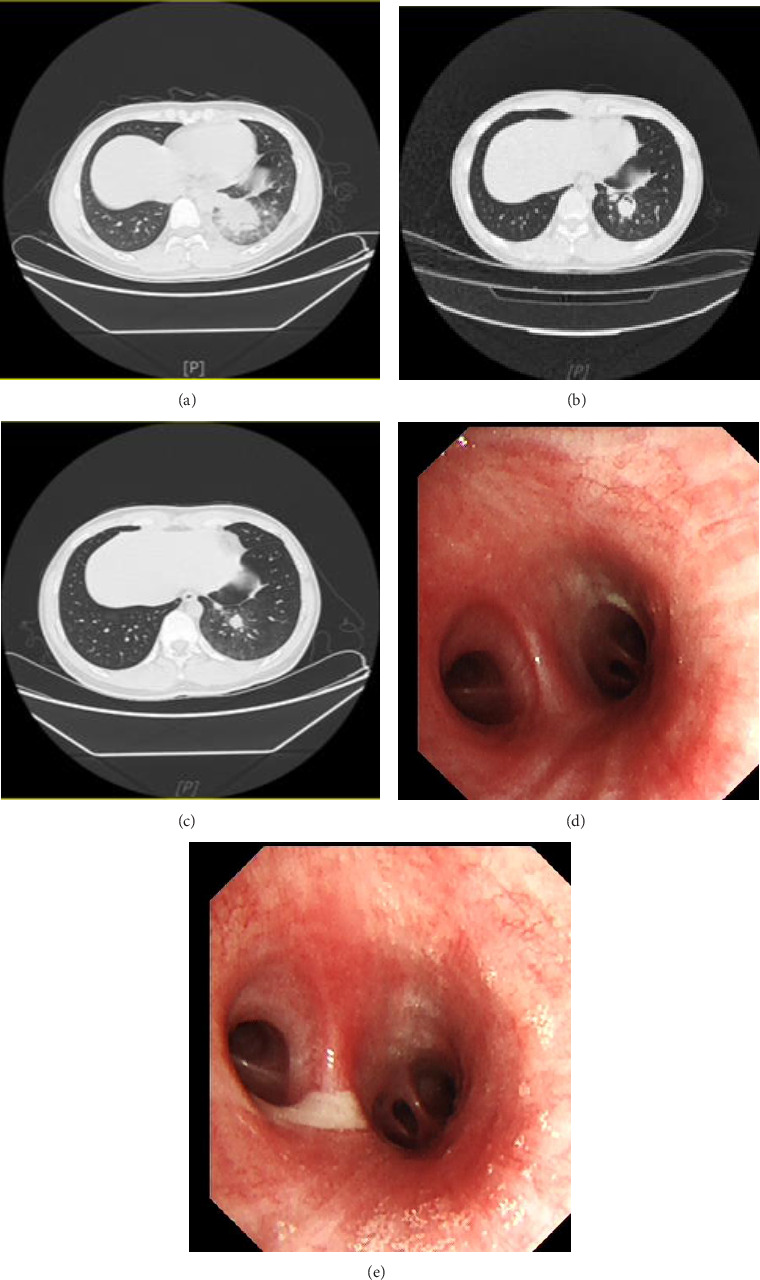

Exogenous lipoid pneumonia (ELP) is a rare disease with both acute and chronic forms. This paper primarily summarizes the diagnosis and treatment process of bronchoalveolar lavage combined with glucocorticoids treatment of acute ELP caused by aspiration of liquid hydrocarbons (e.g., kerosene and diesel fuel) at our hospital. Furthermore, the present study analyzes the advantages of bronchoalveolar lavage combined with glucocorticoids treatment of acute ELP.